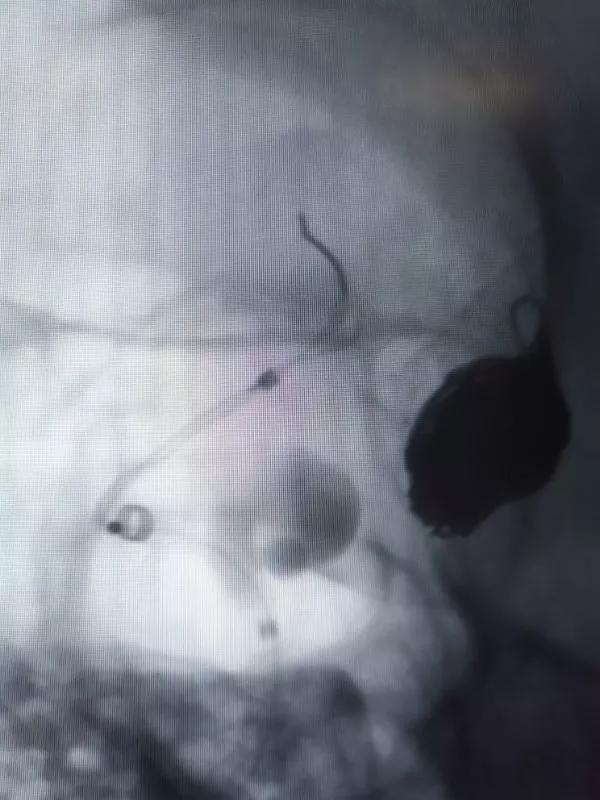

通过导引导管,在Synchro2微导丝的配合下将T-track微导管置入右侧大脑中动脉。

选择4.0×15mm Tubridge®支架,成功释放,覆盖颈内动脉床突上段动脉瘤。

然后再次通过支架并达到右侧大脑中动脉,向海绵窦段多发动脉瘤输送并释放4.0×30mm Tubridge®支架。